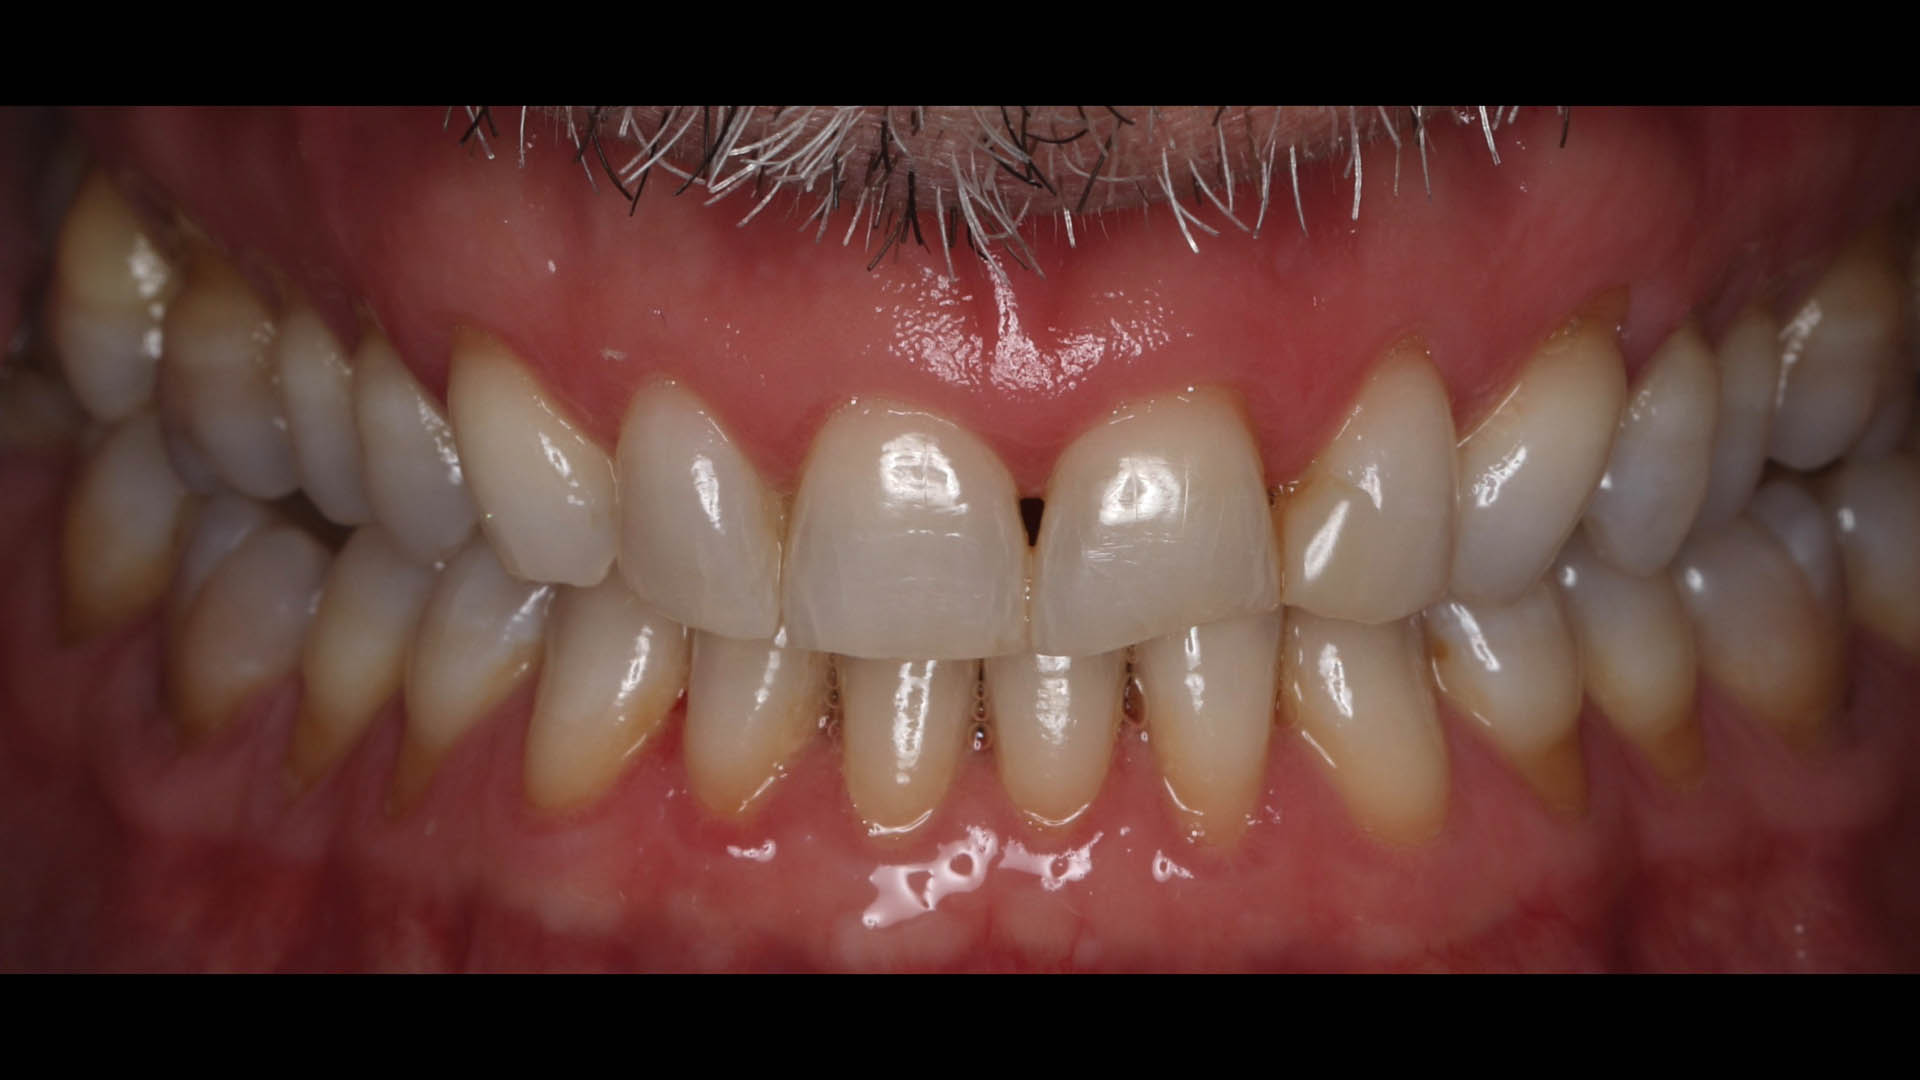

Take a glimpse into the magic of Coral Gables Dentistry through our before and after pictures. See firsthand the incredible smile makeover transformations that have brought confidence and joy to our patients.